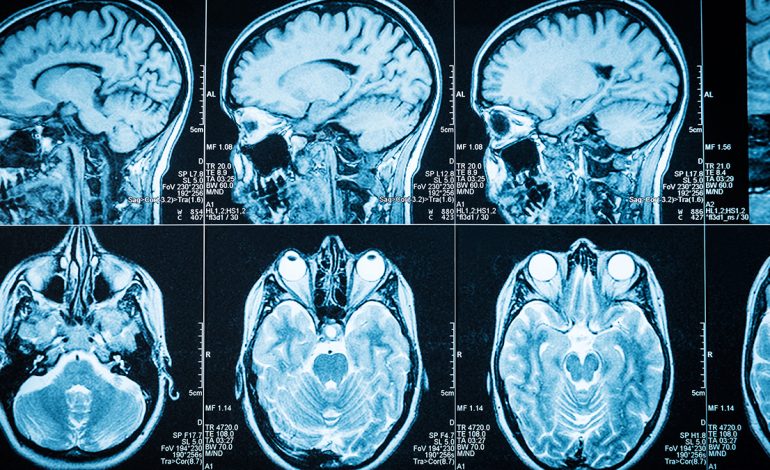

Simptoma kryesore për shumicën e njerëzve me epilepsi janë konvulsionet, që shkaktohen nga rritja e aktivitetit elektrik në tru.